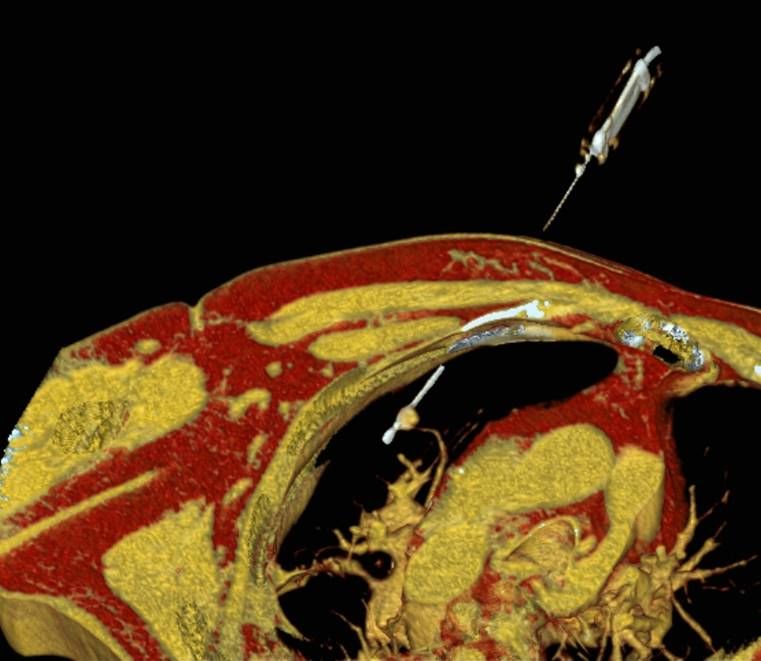

Thermoablation von Lungentumoren

Die minimalinvasive Thermoablation ist auch eine Therapieoption für Lungentumore. Damit ein Lungentumor mit diesem Verfahren effektiv und sicher behandelt werden kann, sollten bestimmte Bedingungen (wie Größe, Anzahl und Lage) erfüllt sein. Ob diese Voraussetzungen gegeben sind, wird das Vorgehen vor der Therapie mit Kollegen aller für diese Fragestellung relevanten Fachdisziplinen besprochen.

Abbildung: Bei der perkutanen Thermoablation von Lungentumoren werden spezielle Applikatoren unter CT-Bildgebung in den Zieltumor eingebracht. Durch Hitze wird der Tumor dann zerstört.